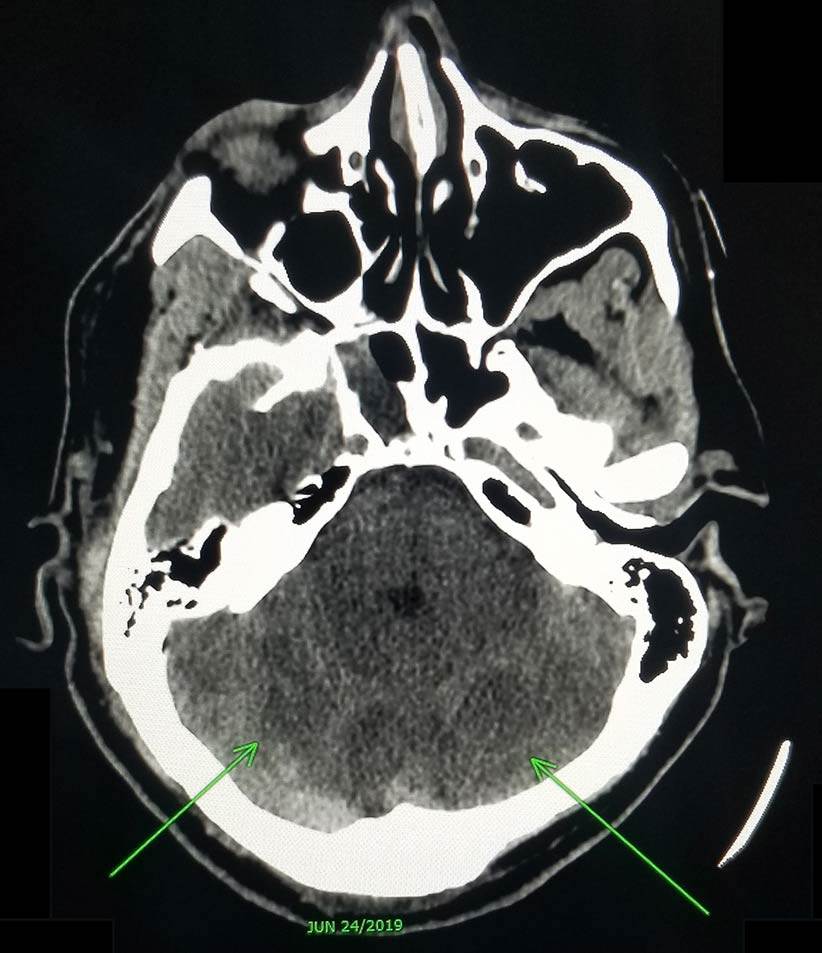

“El paciente estaba haciendo jardinería cuando perdió el conocimiento y fue llevado de emergencia al hospital. Al llegar se le hizo un CT & MRI y MRA (tipo de resonancia magnética que usa un campo magnético e impulsos de energía de ondas de radio para generar imágenes de los vasos sanguíneos) y se observó una isquemia del seno cavernoso. Luego de hacer bien el historial la hermana nos notifica que en la ropa del paciente había varias pastillas de viagra y que su hermano era tomador usual de este medicamento y que ese día muy posiblemente había tomado para una cita que tenía pautada”, dijo el Dr. Ernesto Jimeno a la Revista Medicina y Salud Pública (MSP).

Según los doctores que atendieron el caso en el Hospital Auxilio Mutuo, al paciente se le realizaron varias tomografías computarizadas y resonancias magnéticas que mostraron insultos isquémicos multifocales en evolución en todo el territorio de perfusión de las arterias cerebrales posteriores con edema citotóxico que provocó borramiento de los surcos corticales y pliegue cerebeloso. Además, la prueba de hipercoagulación -para determinar si una persona tiene o ha formado un coágulo sanguíneo- fue positiva para PR-3 pero C-ANCA fue negativa.